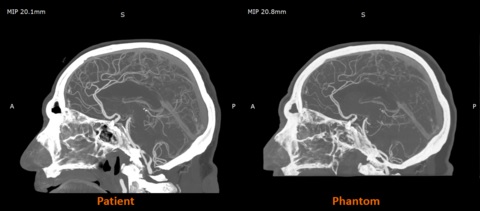

事实上,Stratasys与西门子医疗的早期合作研究显示,RadioMatrix能够以惊人的精度匹配这些数值。据公司数据,在某些测试中,其偏差值可低至1个亨氏单位,这意味着扫描仪几乎无法区分打印模型与真实人体组织的差异。对于任何合成体模而言,这种精密度都极为罕见,而这正是RadioMatrix真正变革性的价值所在。

真实患者影像与体模影像的对比

目前该材料已在英国博蒙特医院等机构投入应用。通过3D打印的脑血管造影模型,医生们正进行影像引导手术的实操培训。这些早期实践表明,具有放射显影特性的打印解剖模型能使培训过程更标准化、可重复性更强,尤其对于需要精准操作微小血管的术式具有显著价值。